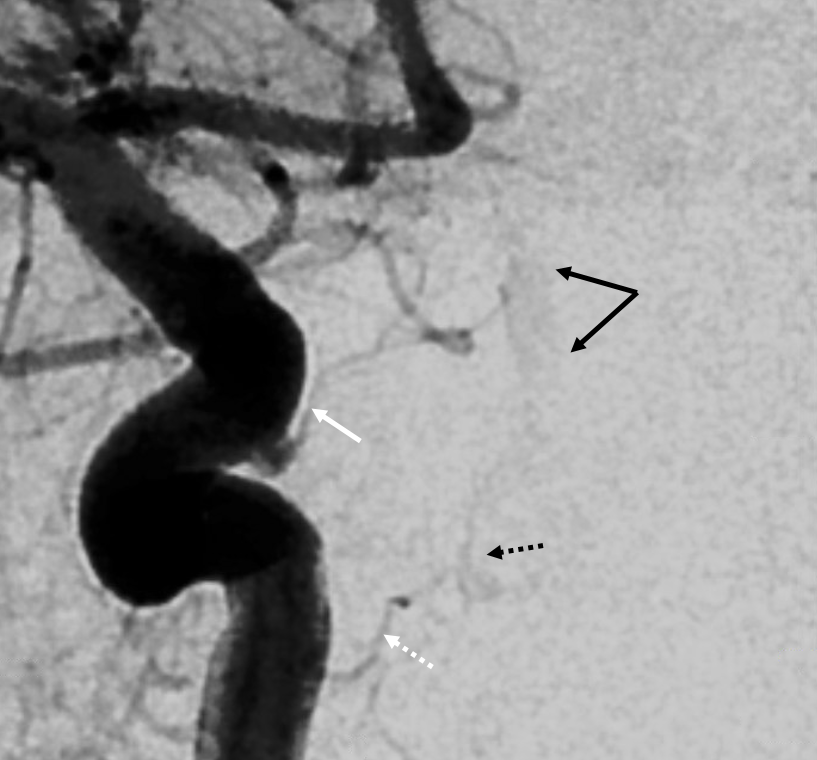

Supply of the Hypophysis and Balance

As always neuroangio is about balance. There may be one or more superior hypophyseal arteries. Usually one is visible by cone beam/flat panel CT. Sometimes more than two. Here there are 3. Nicely shown is supply of the stalk (open arrow). There is also likely contribution to the optic chiasm, which is of course very important. The inferior hypophyseal branches (dashed arrow) from the MHT support the posterior pituitary. The ILT is hypoplastic, with lateral branches of the MHT (white arrowhead) heading towards the meckel cave and the recurrent branch along the tentorial edge (black arrowhead) supplying territory normally done by the ILT

Without labels